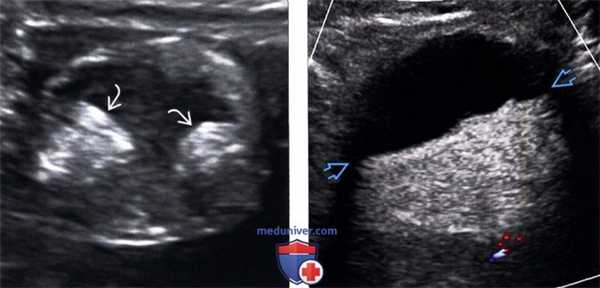

(Слева) На ультрасонографии определяются два узла Рокитанского в жире дермоида, имеющего противоречиво кистозный вид.

(Справа) На цветовой допплерографии определяется плавающий полутвердый - полужид -кий жир в дермоиде, жидкостно-жировой уровень.